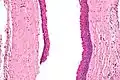

Odontogenic keratocysts have a diagnostic histological appearance. Under the microscope, OKCs vaguely resemble keratinized squamous epithelium;[13] however, they lack rete ridges and often have an artifactual separation from their basement membrane.[2]

The fibrous wall of the cyst is usually thin and uninflamed. The epithelial lining is thin with even thickness and parakeratinised with columnar cells in the basal layer which have focal reverse polarisation (nuclei are on the opposite pole of the cell).[11] The basal cells are an indication of the odontogenic origin as they resemble pre-ameloblasts. The epithelium can separate from the wall, resulting in islands of epithelium. These can go on to form 'satellite' or 'daughter' cysts, leading to an overall multilocular cyst.[9] Presence of daughter cysts is particularly seen in those with NBCCS.[11] Inflamed cysts show hyperplastic epithelium which is no longer characteristic of OKCs and can have resemblance to radicular cysts instead. Due to areas of focal inflammation, a larger biopsy is required for correct diagnosis of odontogenic keratocysts.[9]